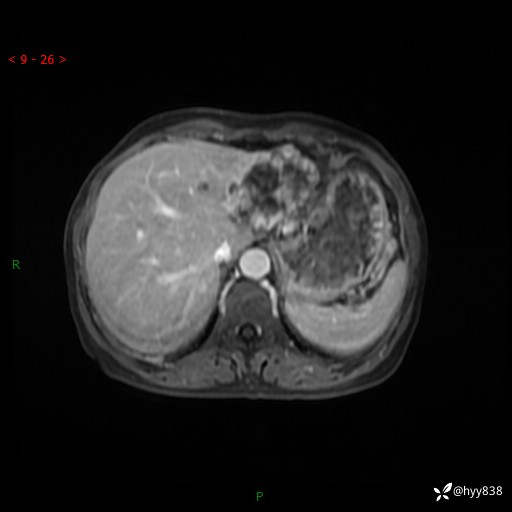

老年女性,偶然发现肝脏占位,综合各个序列,你考虑什么---结果公布

患者年龄:66岁

主诉:发现肝脏占位性病变2天

简要病史:患者2天前因“腰疼”至当地医院就诊时发现肝脏左叶占位性病变,无发热、畏寒,无皮肤黄染,无腹痛、腹泻,无恶心、呕吐、厌油等不适,今进一步诊治遂来我院就诊,门诊以“肝脏占位性病变性质待查”收入我科。 起病以来,患者精神、睡眠一般,饮食欠佳,二便正常,体力、体重无明显减轻,

辅助检查:MRI

临床诊断:肝占位

肝脏MRI平扫(同反相位)

T2WIfs+DWI

增强(动脉期+静脉期+延迟期)